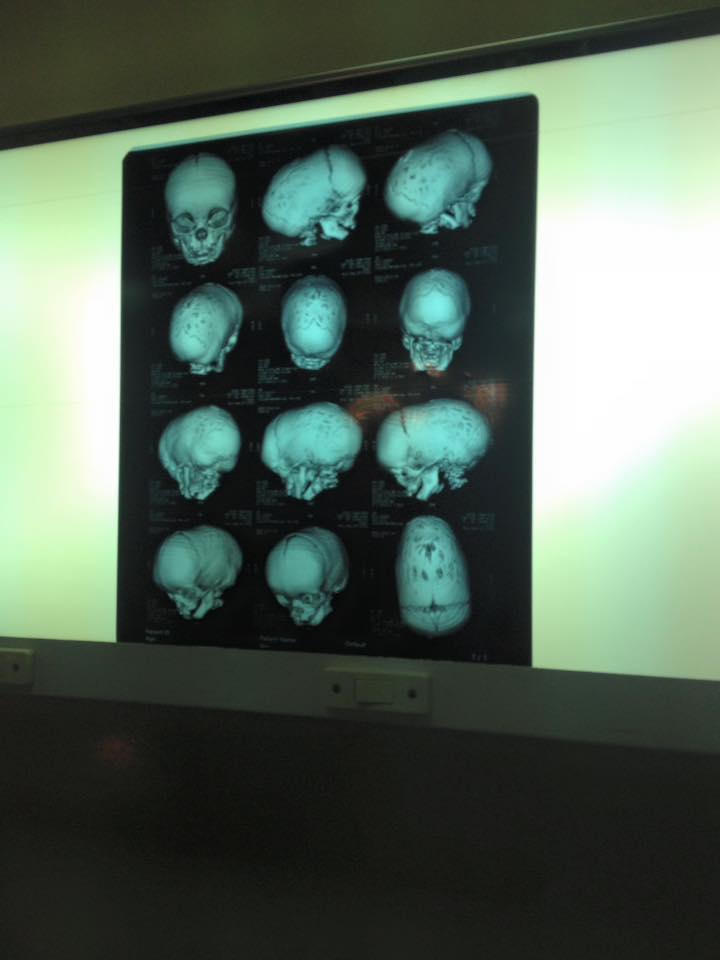

Tại đây các bác sĩ Khoa phẫu thuật thần kinh, Bệnh viện Xanh Pôn phát hiện bé mắc một dị tật hiếm gặp ở vùng sọ não, gọi là đầu dị dạng hình thuyền, khiến cho hộp sọ bị biến dạng. Xương sọ sinh ra có nhiều lỗ hổng tập trung nhiều vùng đỉnh 2 bên, làm khớp dọc giữa không còn dẫn đến sự phát triển bất thường của hộp sọ, xương sọ không phát triển theo chiều ngang, mà lại phát triển mạnh theo chiều trước sau do cơ chế bù trừ của các đường khớp trán đỉnh ở trước và đỉnh chẩm ở sau đẫn đến dị dạng hộp sọ.

Trước khi phẫu thuật xương trán của bệnh nhân biến dạng nhiều, cong lồi nhiều ra trước kéo theo cả cung mày và trần ổ mắt, gây mất cân xứng với khuôn mặt, ảnh hưởng nhiều đến thẩm mỹ. Các bác sĩ cho biết, nếu để lâu, khi các đường khớp phía trước và phía sau không còn phát triển bù trừ được đủ, thể tích hộp sọ của cháu bé, có thể hẹp hơn bình thường sẽ gây tăng áp lực nội sọ.

Theo Ths. BS Nguyễn Đình Hưng – Giám đốc Bệnh viện đa khoa Xanh Pôn- người trực tiếp phẫu thuật cho bé Lam, cho biết, trường hợp cháu bé bị tổn thương luckenschadel skull – còn gọi là đầu dị dạng hình thuyền, do khớp đỉnh 2 bên dính nhau làm đường kính trước sau của hộp sọ kéo dài ra, trong khi đường kính ngang 2 bên hẹp lại. Mục đích của cuộc phẫu thuật là tạo hình, trả lại thẩm mỹ bình thường cho cháu bé, thứ 2 là mở rộng thể tích hộp sọ, giúp hộp sọ không chèn ép thêm vào não, để não của bé phát triển.